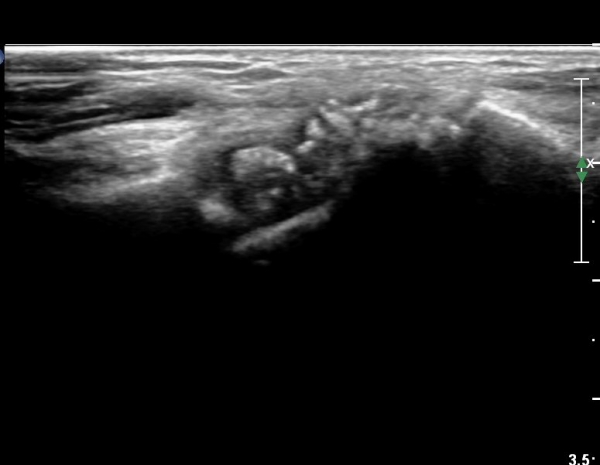

¼ö±Ù°ü Á¾´Ü¸é°Ë»ç¿¡¼ ±¼°î°Ç ½ÉºÎ¿¡ ¼®È¸È¼º À½¿µÀÌ Á¸ÀçÇϰí Àü¹ÝÀûÀÎ ¼öÁö ±¼°î°ÇÀÇ ºñÈÄ, Á¤Á߽ŰæÀÇ ºÎÁ¾°ú

ÈûÁÙ ¹× Á¤Á߽ŰæÀÇ Ç¥ÃþÀ¸·Î ÀüÀ§°¡ °üÂûµÈ´Ù, (»çÁø 5, 6,). ÆÄ¿öµµÇ÷¯°Ë»ç¿¡¼ Ç÷·ùÁõ°¡°¡ °üÂûµÊ´Ù(»çÁø 6).